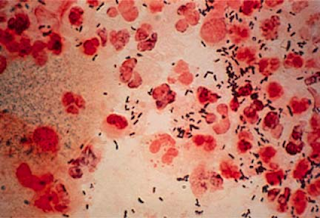

Trikomoniasis menyebabkan keluarnya cairan berbau busuk pada vagina, kelamin gatal, dan nyeri saat buang air kecil pada wanita. Pria biasanya tidak memiliki gejala apa pun. Komplikasi trikomoniasis bagi ibu hamil termasuk risiko kelahiran prematur.

Gejala pada wanita biasanya muncul antara 5 sampai 28 hari setelah terpapar. Akan tetapi gejala tersebut dapat juga muncul dalam waktu beberapa bulan bahkan bertahun-tahun kemudian. Solusi Tepat Mengobati Kencing Nanah Infeksi dapat ditularkan kepada orang lain meskipun mereka tidak mengalami gejala apapun. Gejala yang ditimbulkan oleh trikomoniasis ini antara lain :- Pada wanita,trikomoniasis dapat menyebabkan vaginitis (peradangan pada vagina). Sedangkan pada pria dapat menyebabkan urethritis (peradangan pada saluran kencing) di dalam penis.

- Keluarnya nanah berwarna kuning kehijau-hijauan atau abu-abu dari vagina (bahkan terkadang berbusa).

- Pada pria biasanya keluar nanah dari penis.